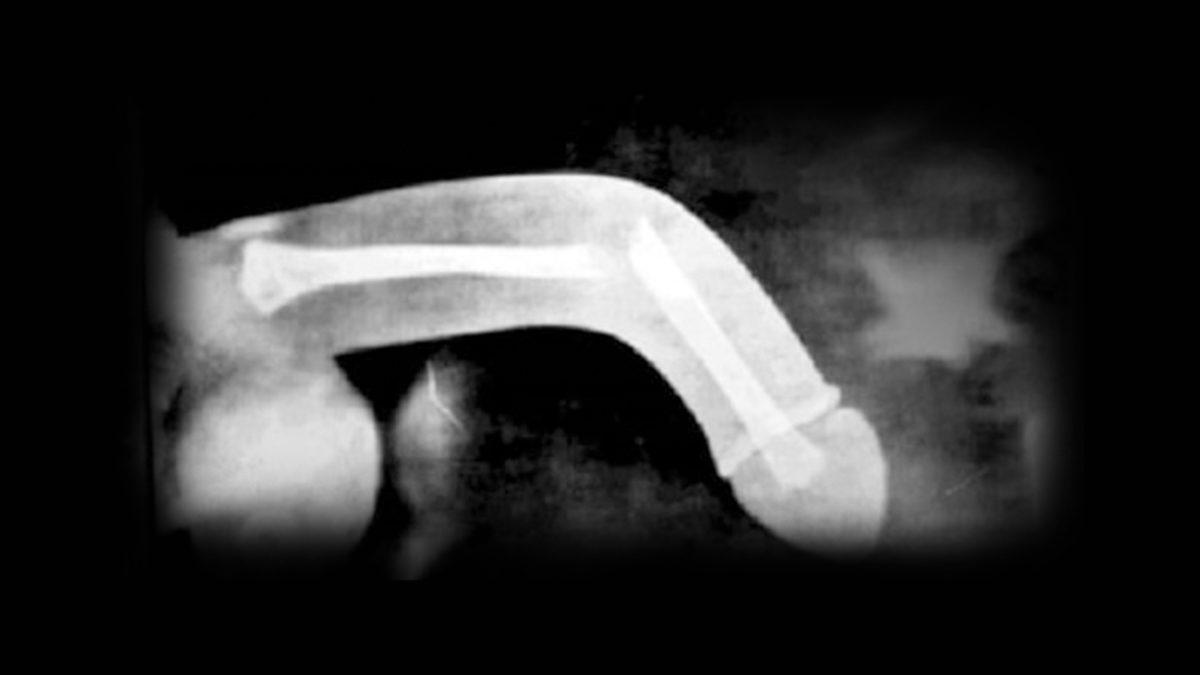

Anatomik olarak penis kemik yapı içermez; iki adet kavernöz cisim denen, içinde kan dolması ile ereksiyonu sağlayan yapılar ve idrar kanalını(üretrayı) içeren spongioz cisimden oluşur. Travmanın büyüklüğüne göre aynı anda spongioz cisim de zarar görür ve idrar yolu yaralanması(yırtılması) oluşabilir.

Penis kırılmaları genellikle ameliyat gerektirir. Cerrah, tunika albuginea ve korpus kavernozum'daki yırtığı kapatmak için dikiş kullanacaktır. Ameliyat esnasında yırtılan veya yaralanan dokular tamir edilir, eğer damarsal yaralanma varsa mikrocerrahi ile damar anastomozu yapılması da gerekebilir.